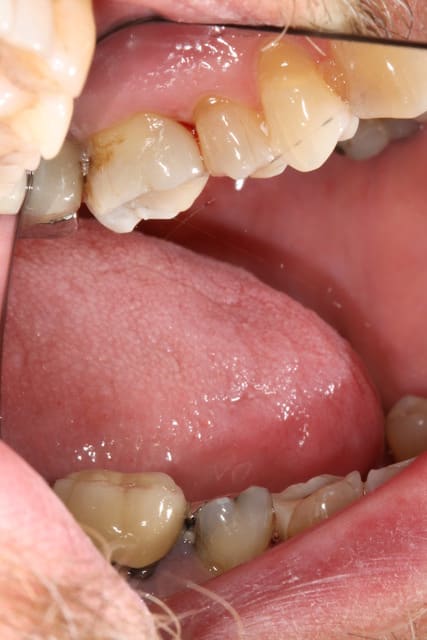

Importance d'une bonne communication, d'information. Dommage qu'on ne sorte pas de la fac avec un minimum. Je ne regrette pas l'investissement dans l'APN.

Photo 1. Moi: "Voilà pourquoi il vous faut un onlay."

Photo 3. Le patient: "Ah quand même! Ben on va faire les autres alors!"